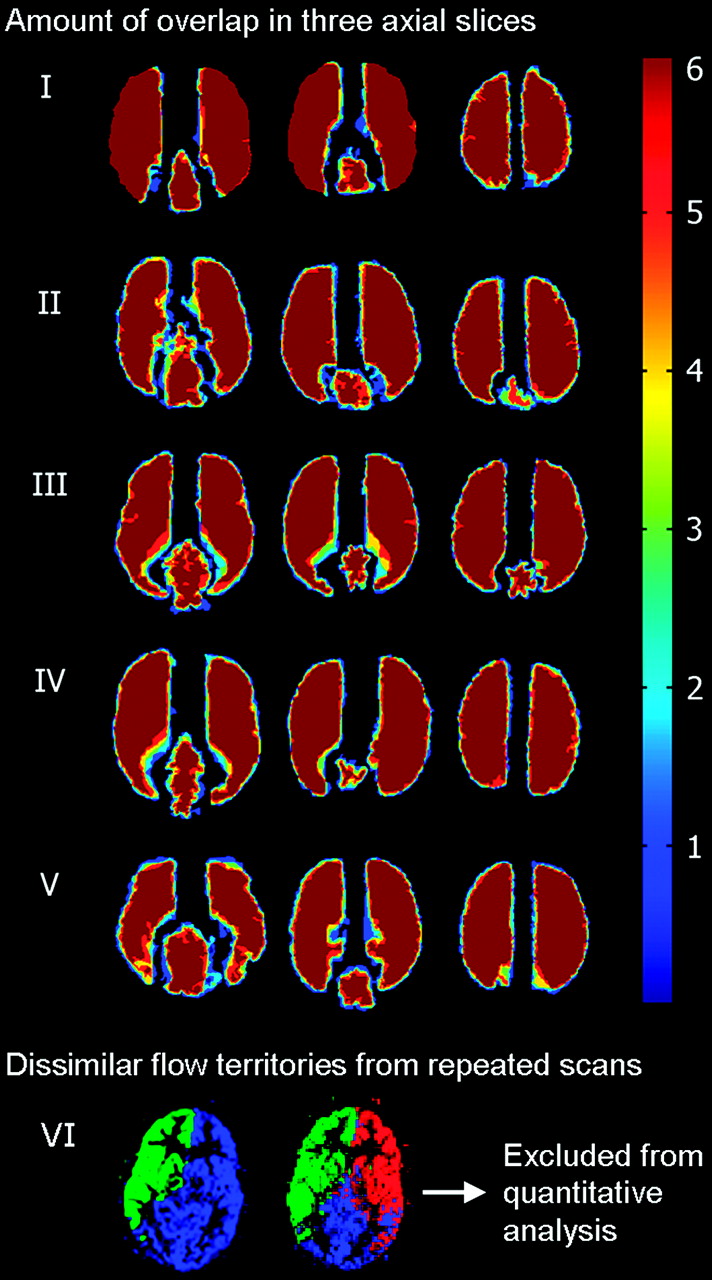

All controls and 8 patients were included in the quantitative reproducibility analysis. Intra- and intercenter repeated planning-free selective ASL yielded comparable flow territories in 34 of 36 datasets (94%). In 1 individual, 2 of 6 scans showed an erroneously enlarged posterior perfusion territory, taking over approximately half of the perfusion territory of the left ICA (Fig 4). This volunteer was not included in quantitative reproducibility analysis. Thirty datasets were included in this analysis. The amount of overlap between the perfusion territories that were gathered from all 6 sessions for the remaining 5 control subjects in our study is shown in Fig 4. In the Table, the results of the quantitative reproducibility analysis are presented. Flow-territory boundaries deviated <4 mm on average and approximately 3 voxels maximum.

Three axial sections in 5 volunteers who were included in the quantitative analysis show the amount of overlap of flow territories from all sessions and sites (dark blue 1, light blue 2, green 3, yellow 4, red 5, and dark red 6 territories overlapping) and dissimilar flow territories obtained from repeat scanning in 1 volunteer who was excluded from further analysis.